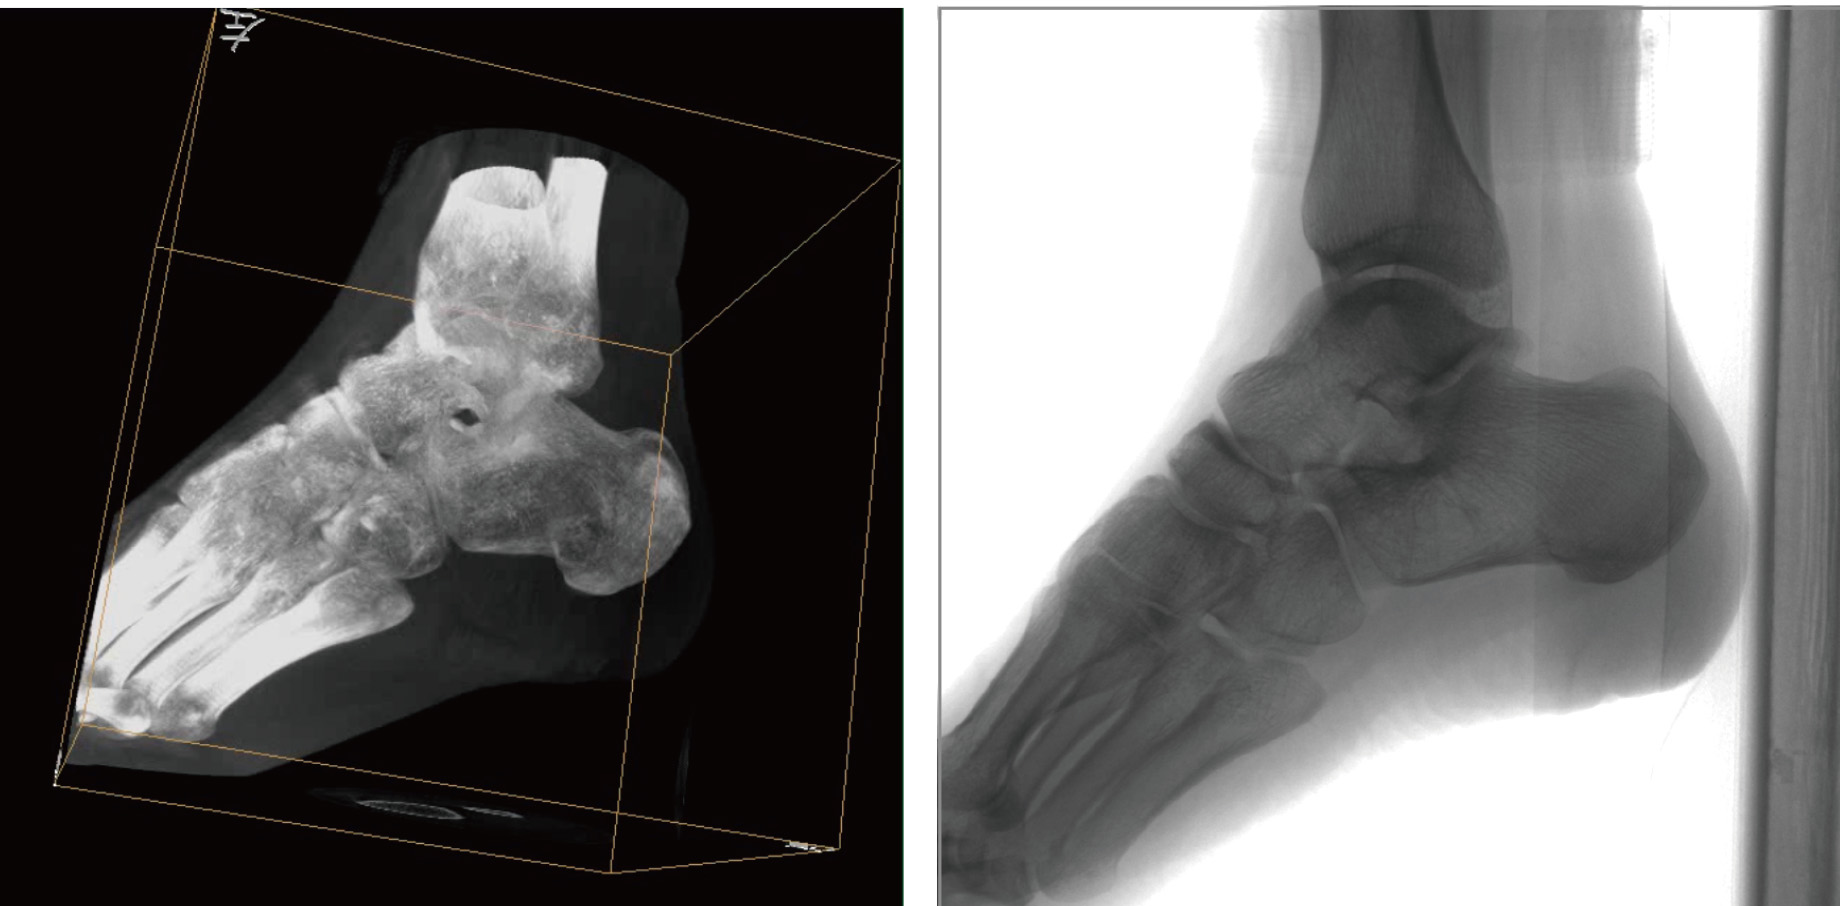

普愛醫(yī)療天弓PLX7500骨科三維C形臂,作為“術(shù)中CT”,在手術(shù)中快速生成類CT斷層圖像和立體三維圖像,為醫(yī)者提供更全面的圖像信息,能夠準(zhǔn)確地觀察植入物的情況,例如螺釘內(nèi)固定術(shù)入釘?shù)奈恢煤徒嵌取L旃璓LX7500三維C形臂性能特點(diǎn):

PLX7500骨科三維C形臂通過(guò)采集,能在術(shù)中快速地生成橫斷面、矢狀面、冠狀面和可旋轉(zhuǎn)的立體圖像,給術(shù)者提供360°無(wú)死角的觀察角度,準(zhǔn)確判斷骨組織和植入物的情況,為手術(shù)的實(shí)施提供保障,極大提高手術(shù)成功率,減少并發(fā)癥概率。